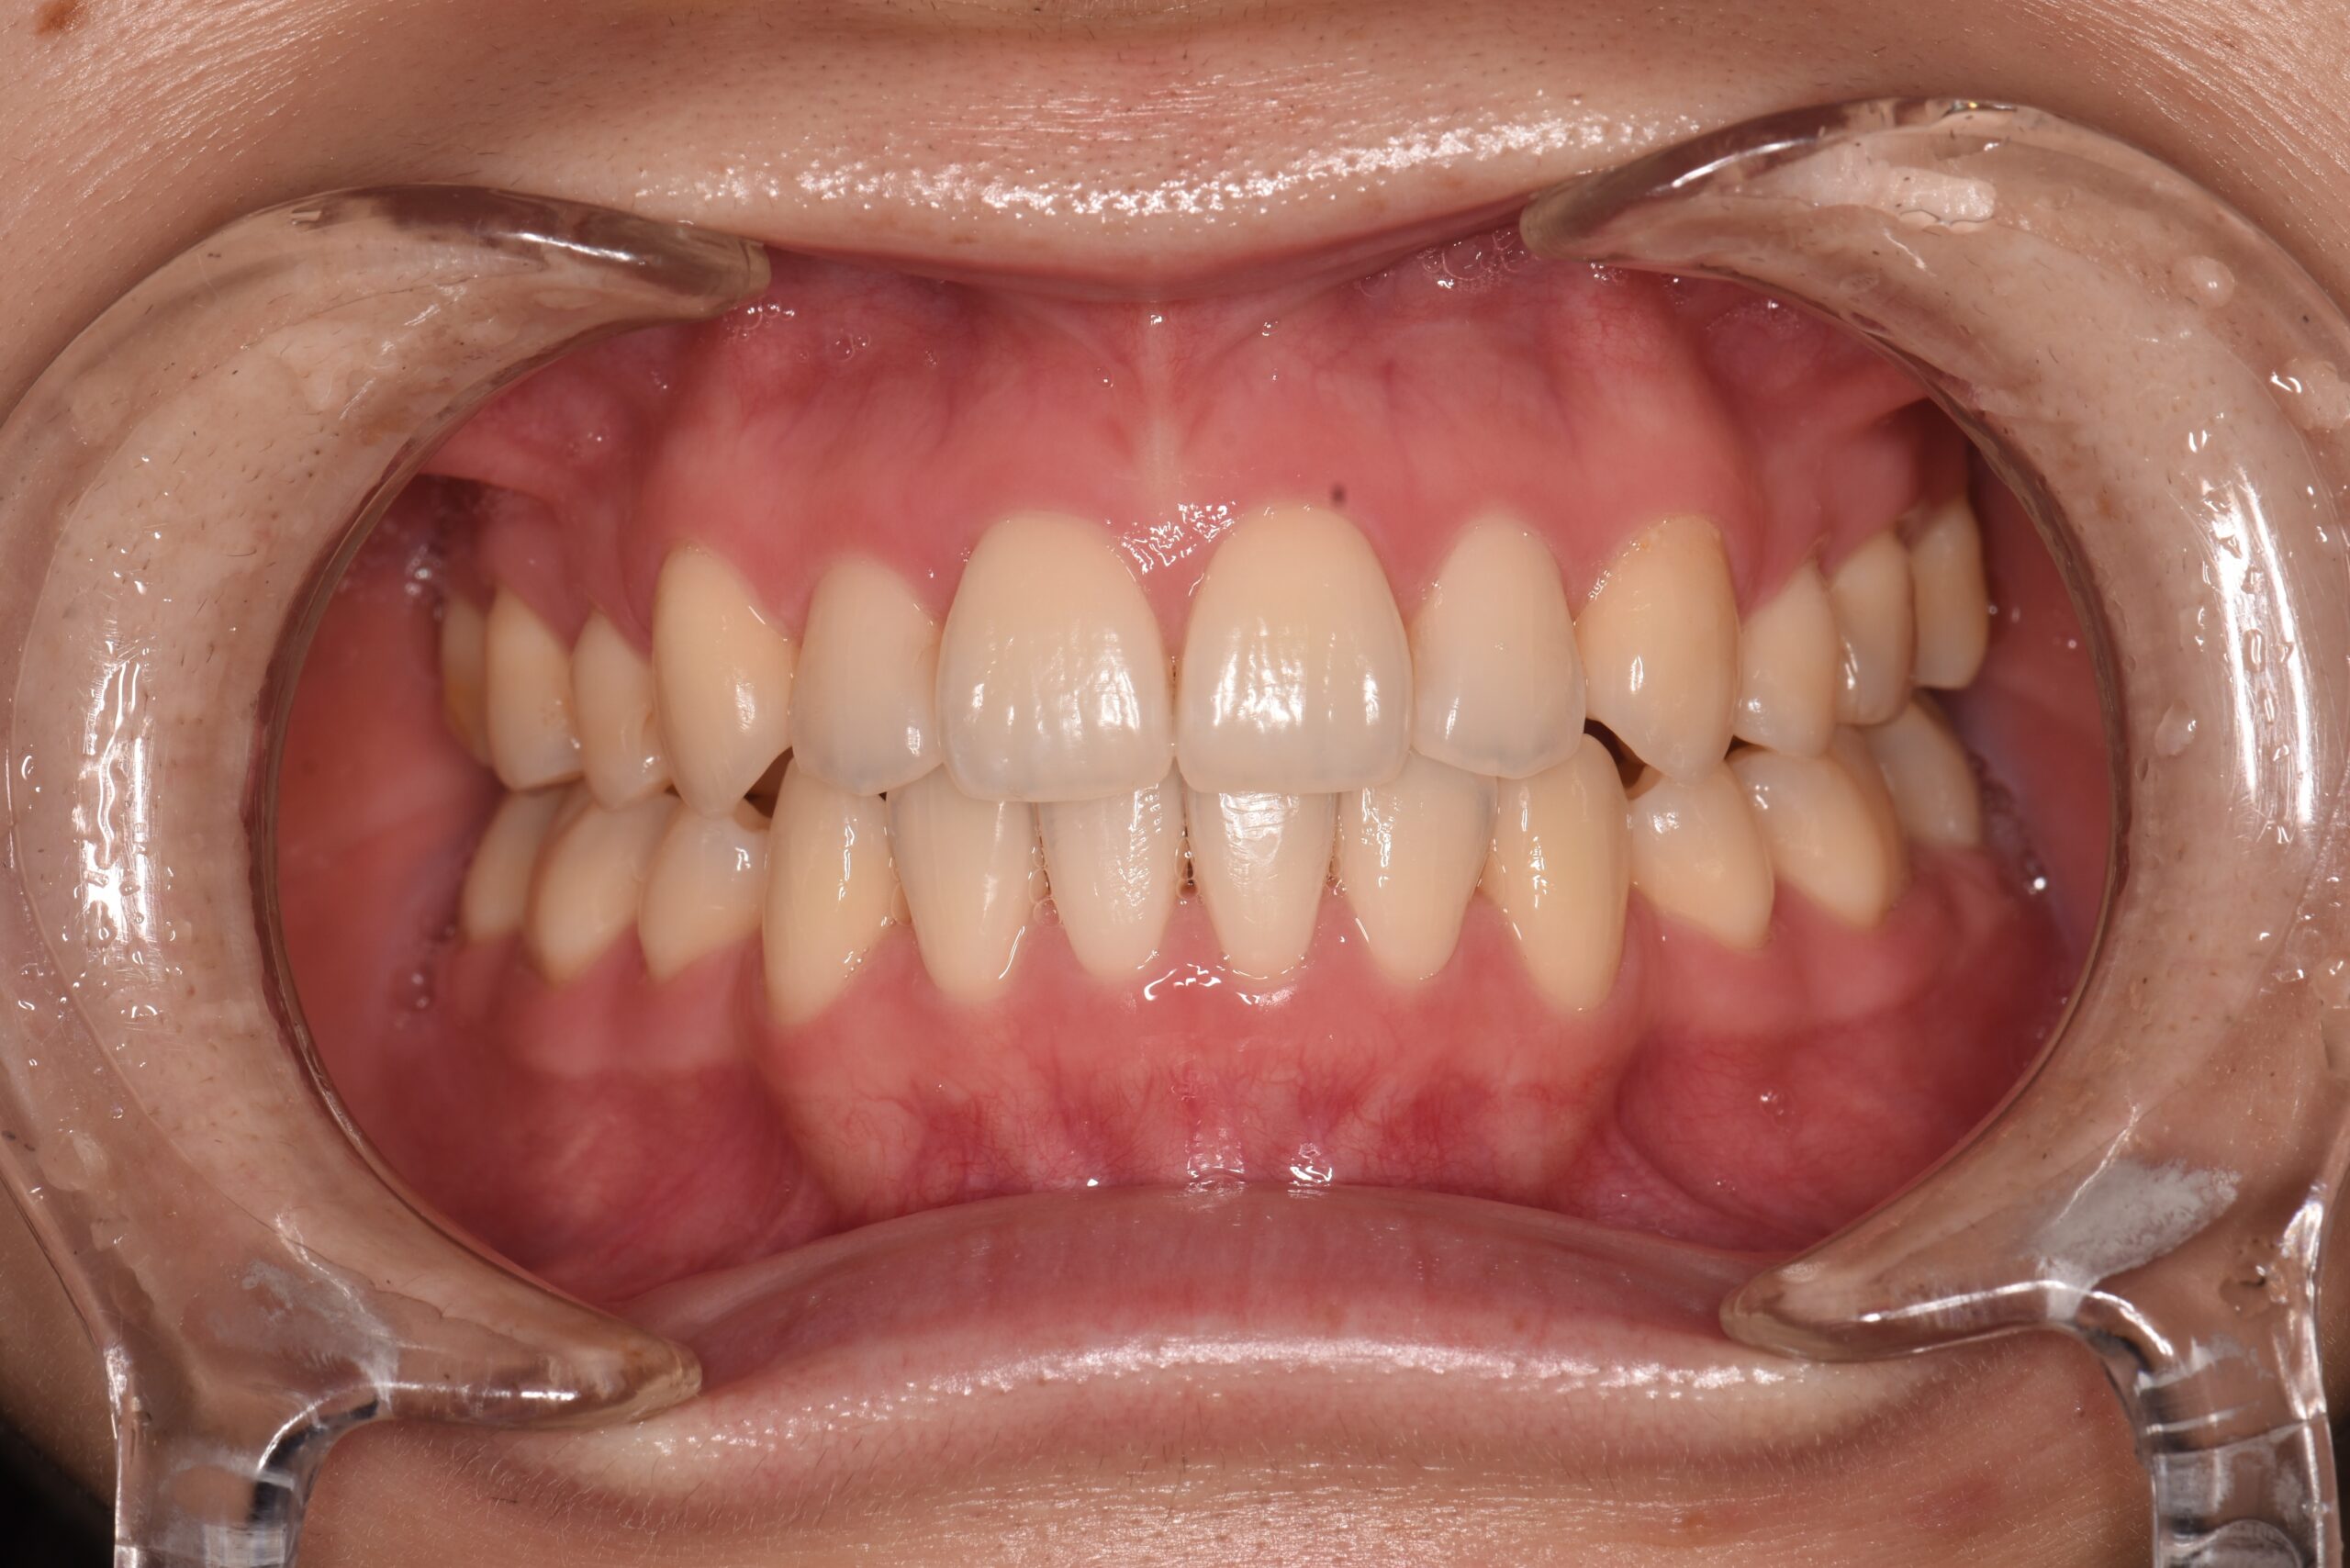

上の前歯が他の歯に比べて前に突き出ている状態です。

見た目のお悩みに限らず、口が閉じにくいためお口の中が乾燥して菌が繁殖し、むし歯や歯周病のリスクが高まります。